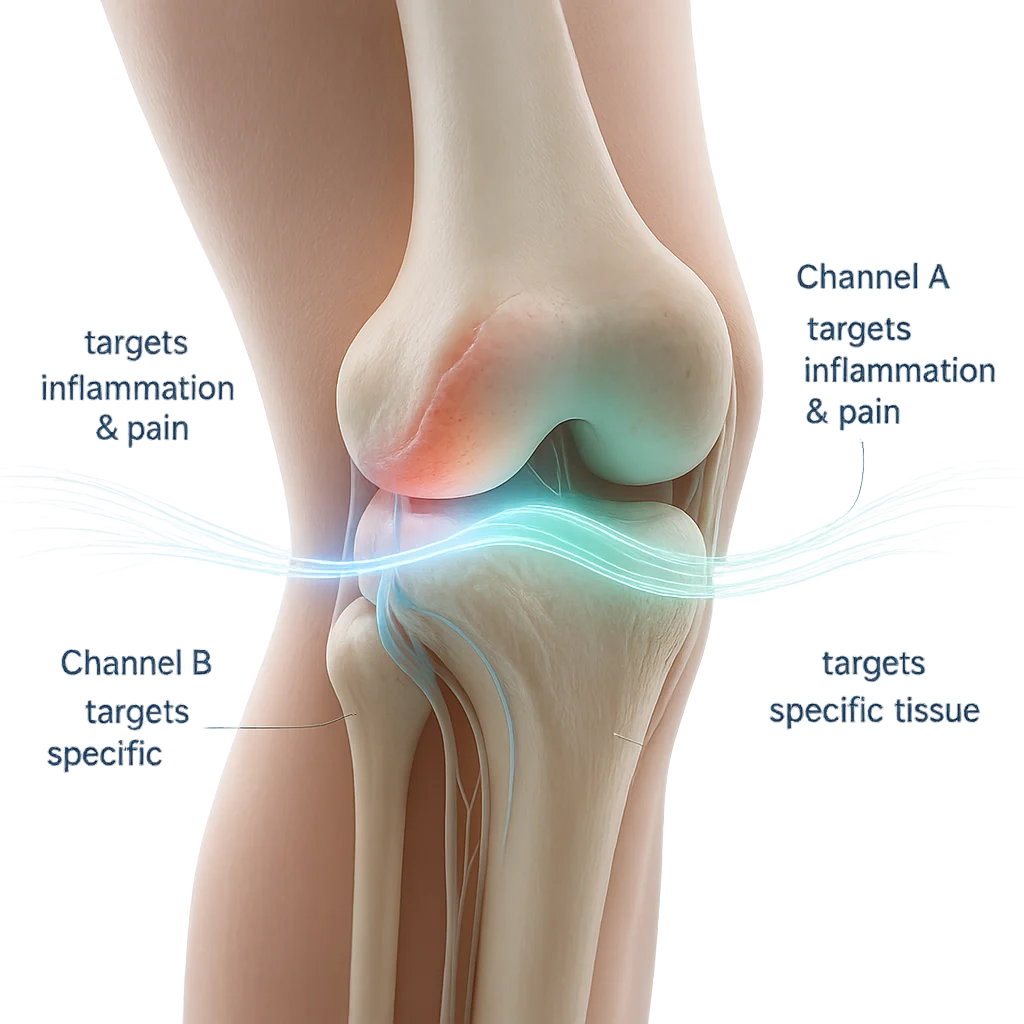

How Does FSM Work?

Picture each tissue in the body, nerve, muscle, fascia, cartilage as having its own unique frequency, like a radio channel.

FSM uses two channels simultaneously, When these two are paired correctly, the tissue responds, inflammation reduces, and healing accelerates far beyond conventional therapy.

Channel 1 → Targets the Problem

Examples:

- Inflammation

- Scar tissue

- Congestion & detox

- Edema

- Something torn & broken

Examples:

- Nerve

- Fascia

- Joint capsule

- Ligament

- Cartilage